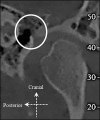

Material and methods: Using Newtom VGi (QR Verona, Italy), 106 cone-beam computed tomography examinations (212 temporomandibular joint areas) of both genders were retrospectively and randomly selected. Two observers examined the images and subsequently classified by consensus the petrotympanic fissure morphology into the following three types: type 1 - widely open; type 2 - narrow middle; type 3 - very narrow/closed.

Results: The petrotympanic fissure morphology was assessed as type 1, type 2, and type 3 in 85 (40.1%), 72 (34.0%), and 55 (25.9%) cases, respectively. No significant difference was found between left and right petrotympanic fissure morphology (Kappa = 0.37; P < 0.001). Furthermore, no significant difference was found between genders, specifically P = 0.264 and P = 0.211 for the right and left petrotympanic fissure morphology, respectively. However, the ordinal logistic regression analysis showed that males tend to have narrower petrotympanic fissures, in particular OR = 1.58 for right and OR = 1.5 for left petrotympanic fissure.